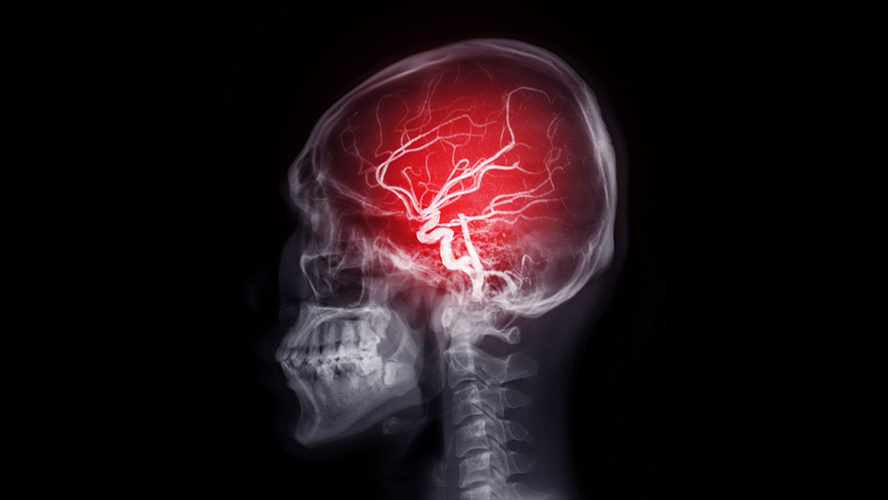

A team led by Dr. Philippe Monnier at UHN’s Krembil Brain Institute (KBI) has uncovered a promising new target that could help limit brain injury following an ischemic stroke—a type of stroke caused by a blood clot.

In a healthy brain, the blood-brain barrier acts like a filter, controlling which substances can enter or leave the brain, thereby protecting the brain from harmful substances. After a stroke, some proteins—like one called RGMa—can change the structure of blood vessel walls in the brain. These changes compromise the vessels’ integrity and make them more permeable, or “leaky”, allowing harmful substances in the blood to enter the brain where they cause damage.